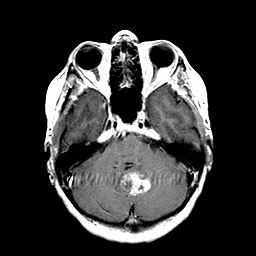

Metastatic Adenocarcinoma of the Colon: T1-weighted MR -- Slice #7

[Home][Help][Clinical] Slice 7